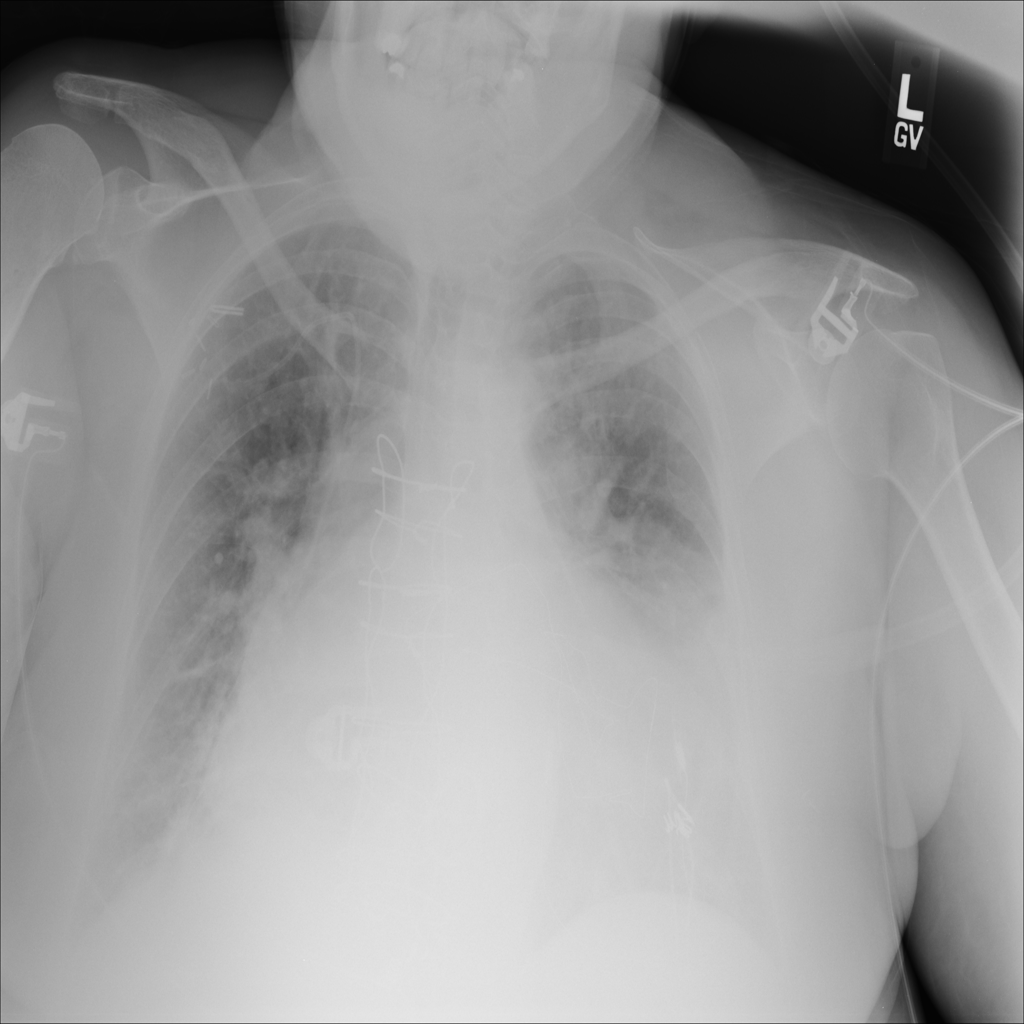

PAT-3384 · IMG-029Cardiomegaly

PAT-3384 · IMG-029

AP